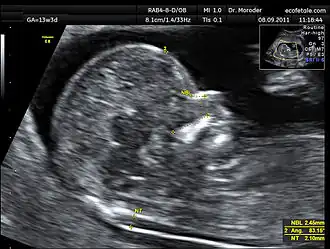

A nuchal scan or nuchal translucency (NT) scan/procedure is a sonographic prenatal screening scan (ultrasound) to detect chromosomal abnormalities in a fetus, though altered extracellular matrix composition and limited lymphatic drainage can also be detected.[1]

Procedure

Nuchal scan (NT procedure) is performed between 11 and 14 weeks of gestation, because the accuracy is best in this period. The scan is obtained with the fetus in sagittal section and a neutral position of the fetal head (neither hyperflexed nor extended, either of which can influence the nuchal translucency thickness). The fetal image is enlarged to fill 75% of the screen, and the maximum thickness is measured, from leading edge to leading edge. It is important to distinguish the nuchal lucency from the underlying amniotic membrane.[9]

Normal thickness depends on the crown-rump length (CRL) of the fetus. Among those fetuses whose nuchal translucency exceeds the normal values, there is a relatively high risk of significant abnormality.